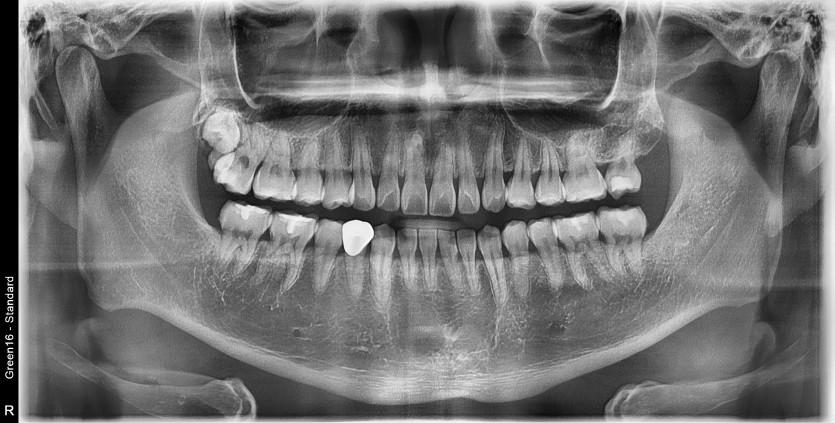

#18사랑니 발치 + #19 과잉치발치